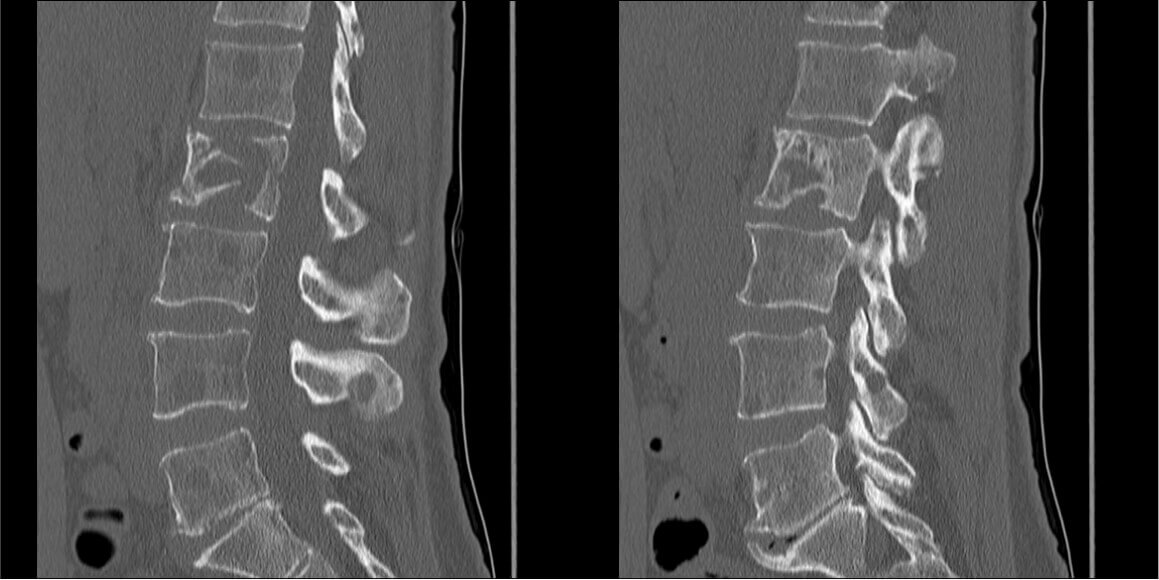

При МРТ обнаружена следующая картина:

Рис. 1 — отмечается литическое поражение тел позвонков поясничного отдела, поражение остистого отростка позвонка L3, патологический перелом тела L1.